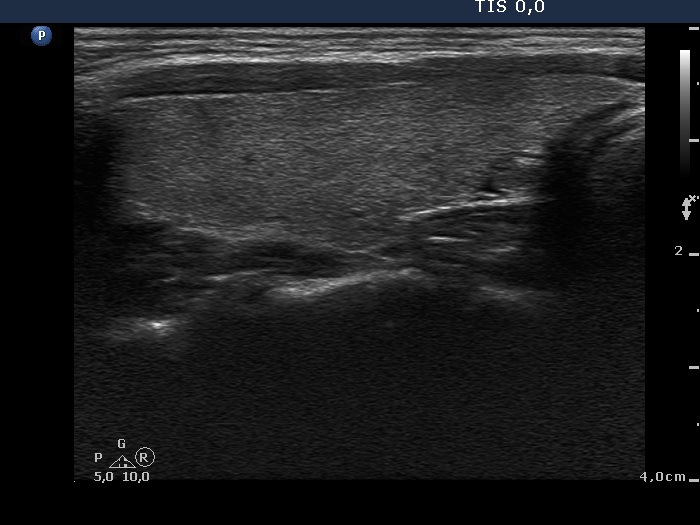

Teamwork - case 791 (ultrasonographic picture 5)

Left lobe, longitudinal scan.